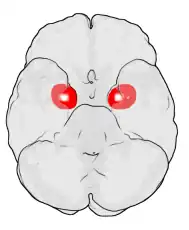

Proyección de la Amígdala (en rojo) sobre la superficie inferior del encéfalo. Dibujo esquemático.